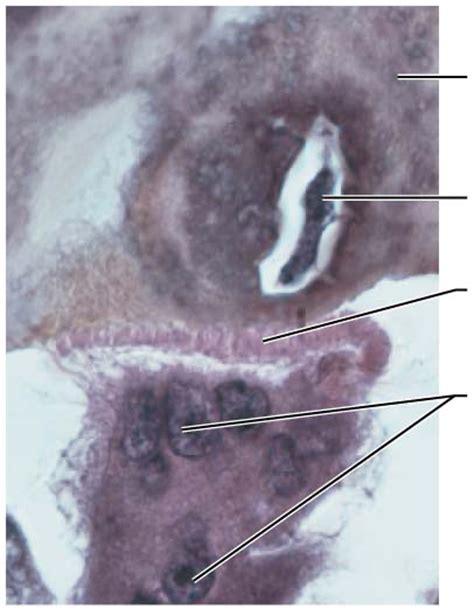

Osteoclast Diagram | Quizlet

Source: o.quizlet.com